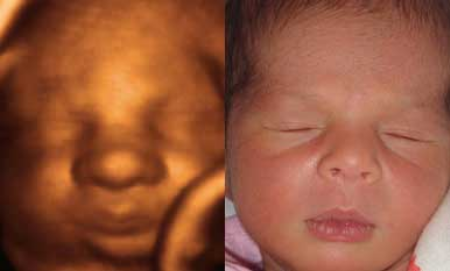

Antes y Después Antes y Después Boxeando Feto de 16 Semanas